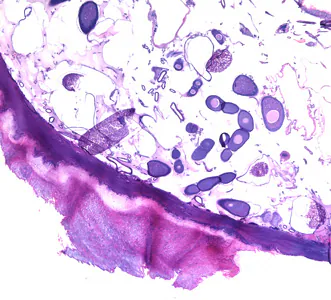

Tunga penetrans lesions and biopsy specimens.

and seek out a warm-blooded host for blood meals. Both males and females feed intermittently on their host, but only mated females burrow into the skin (epidermis) of the host, where they cause a nodular swelling

. Females do not have any specialized burrowing organs, and simply claw into the epidermis after attaching with their mouthparts. After penetrating the stratum corneum, they burrow into the stratum granulosum, with only their posterior ends exposed to the environment

. The female fleas continue to feed and their abdomens extend up to about 1 cm. Females shed about 100 eggs over a two-week period, after which they die and are sloughed by the host’s skin. Secondary bacterial infections are not uncommon with tungiasis.